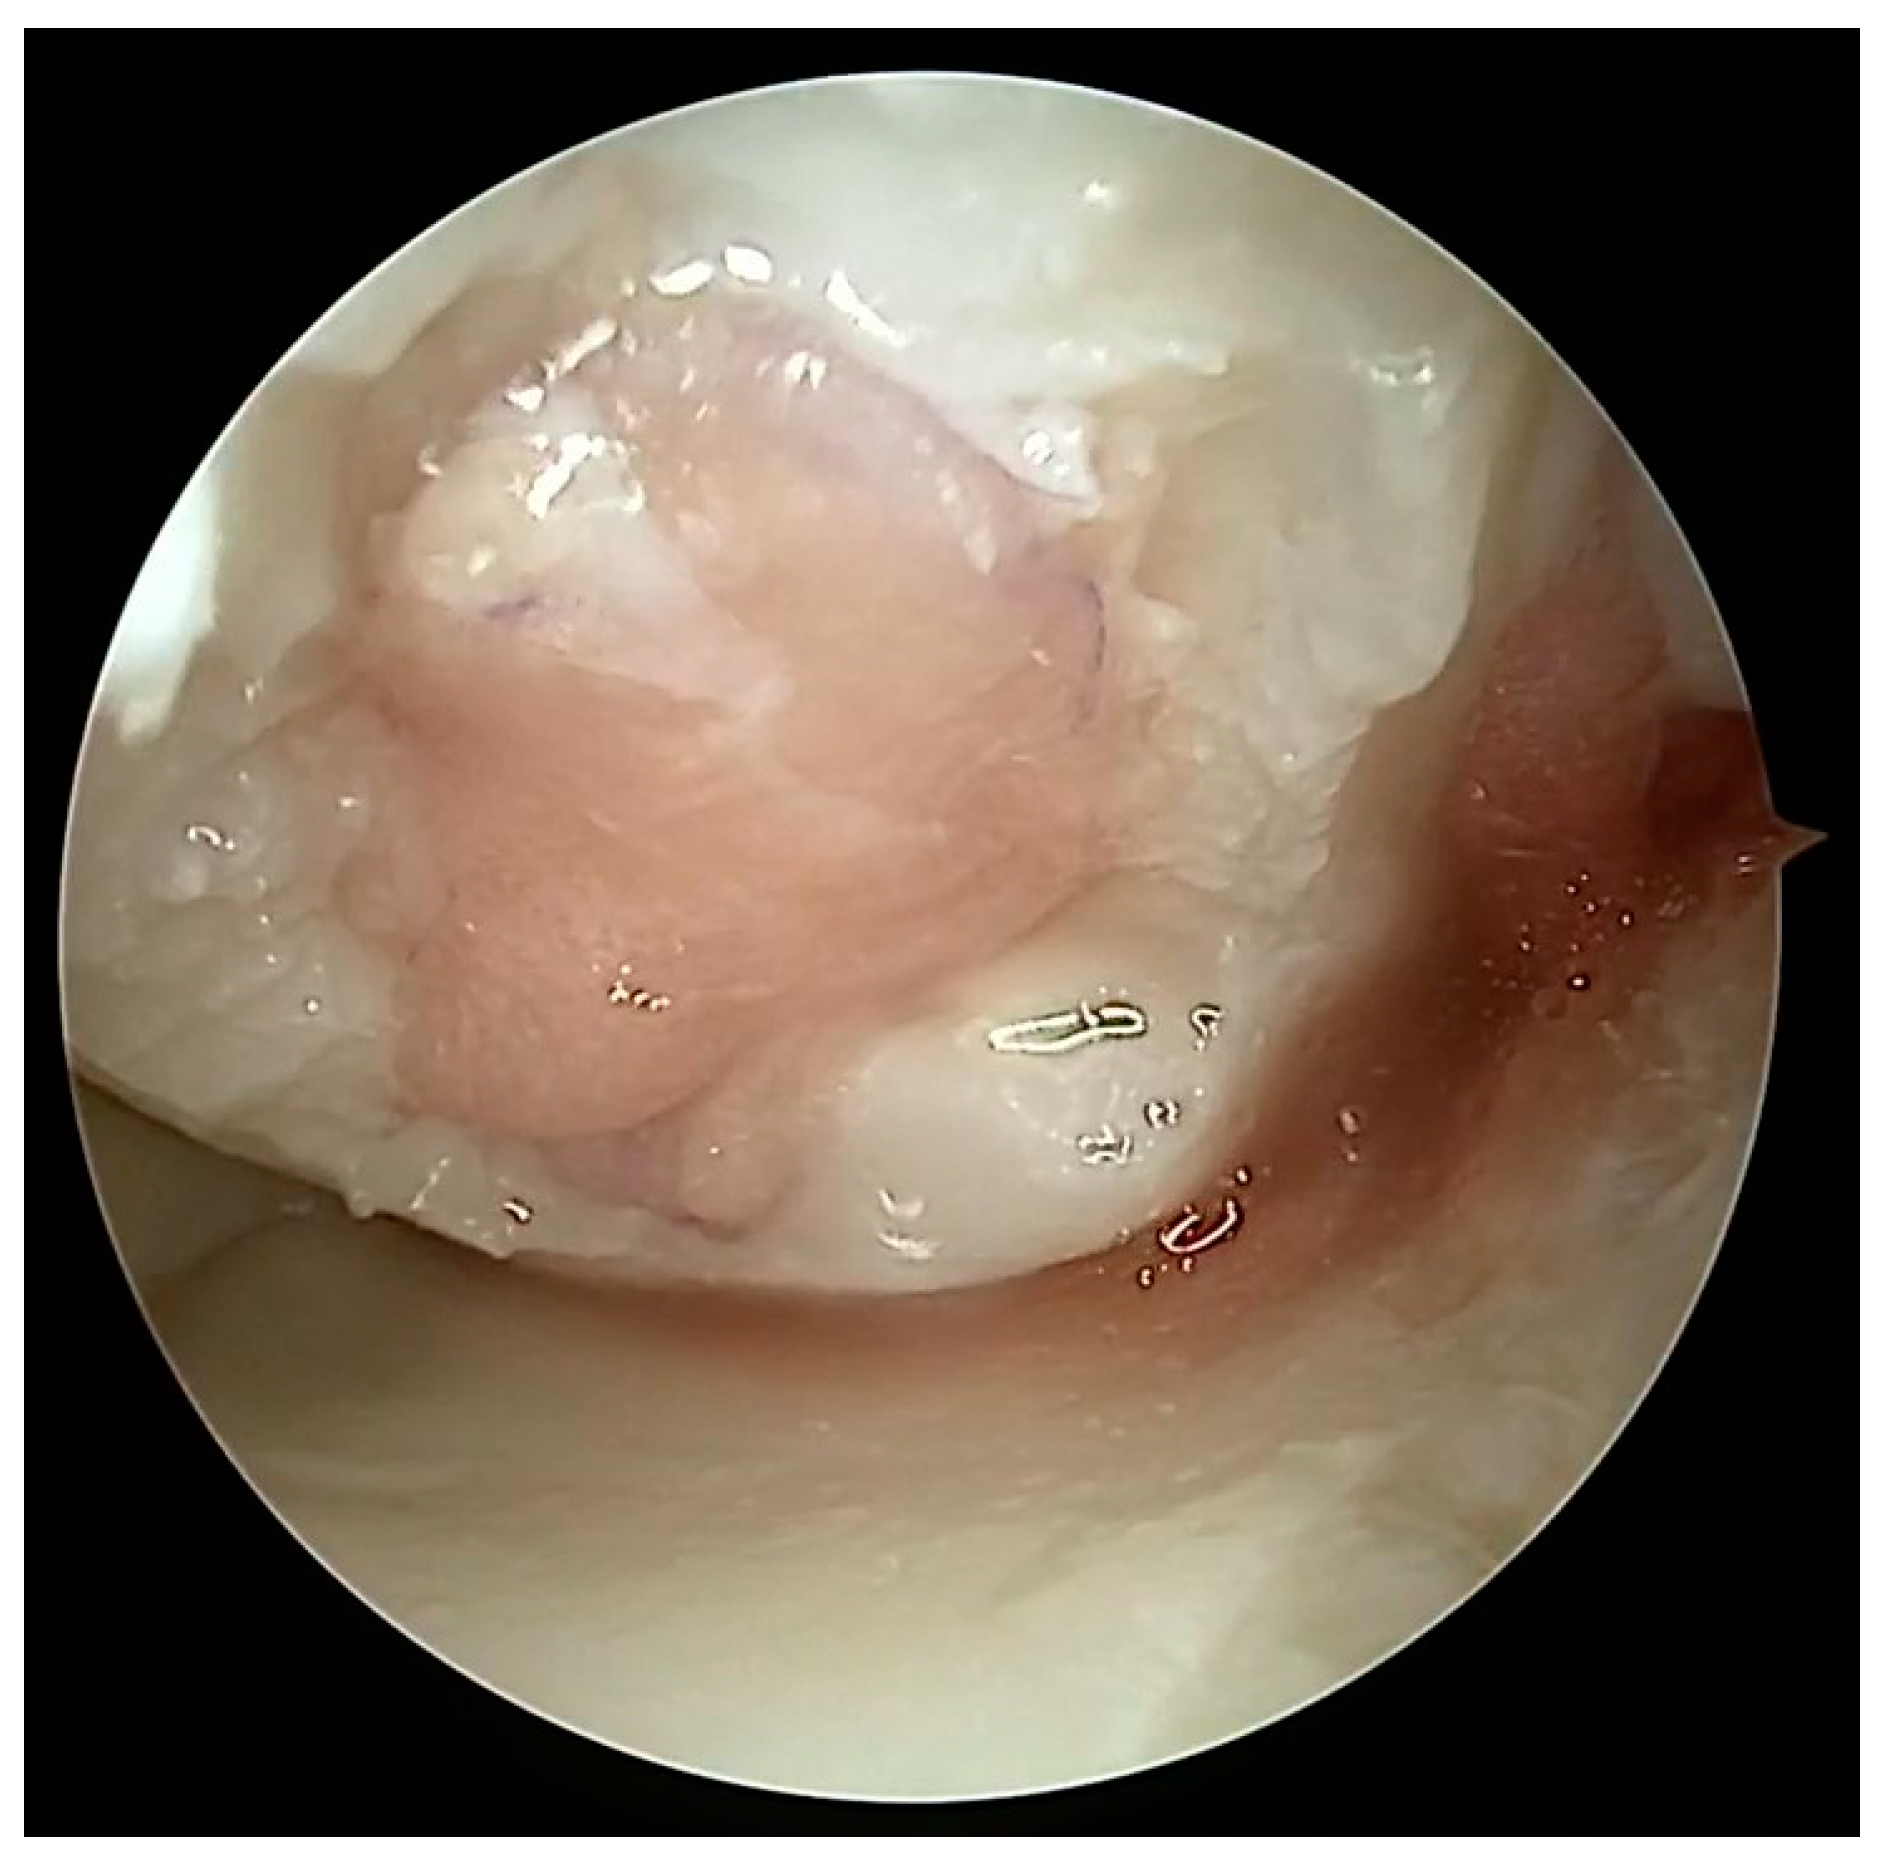

5.1. Microfracture

5.2. Autologous Matrix-Induced Chondrogenesis (AMIC)